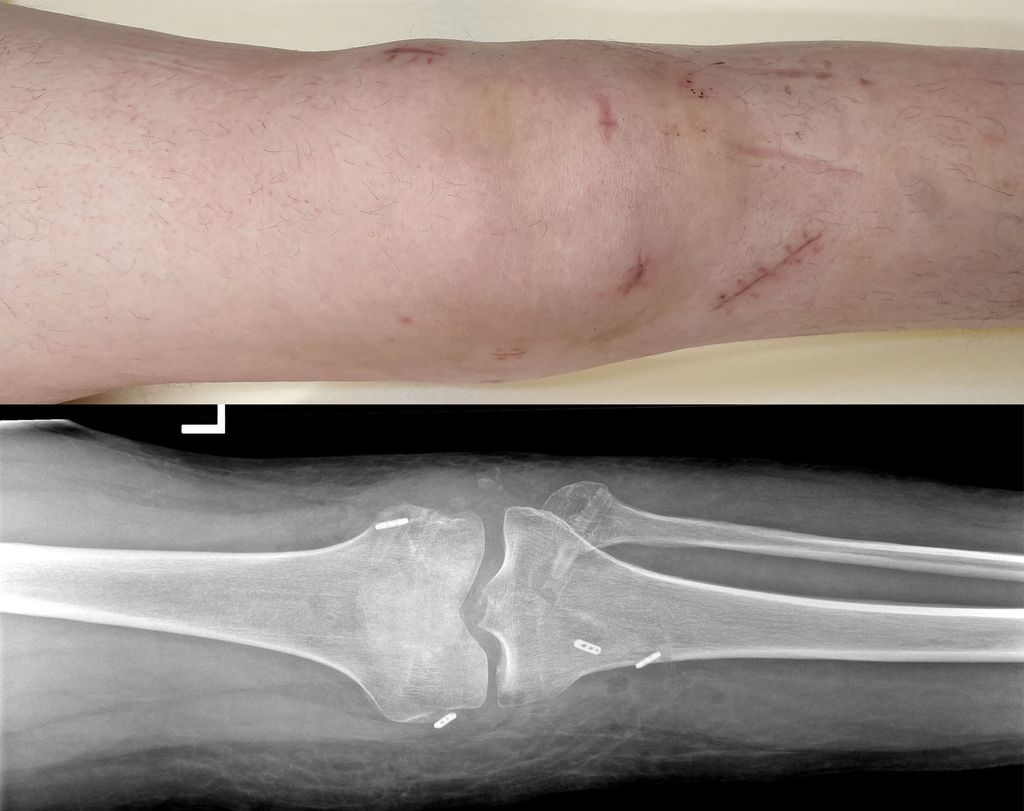

In der Regel wird bei multiligamentären Kniegelenksverletzungen zweizeitig vorgegangen. Hierbei werden primär, innerhalb von 2 Wochen, der mediale und der laterale Bandkomplex (periphere Pfeiler) und sekundär nach ca. 6–8 Wochen das VKB und HKB mittels Auto- oder Allograft rekonstruiert (Abb.3, 4).12